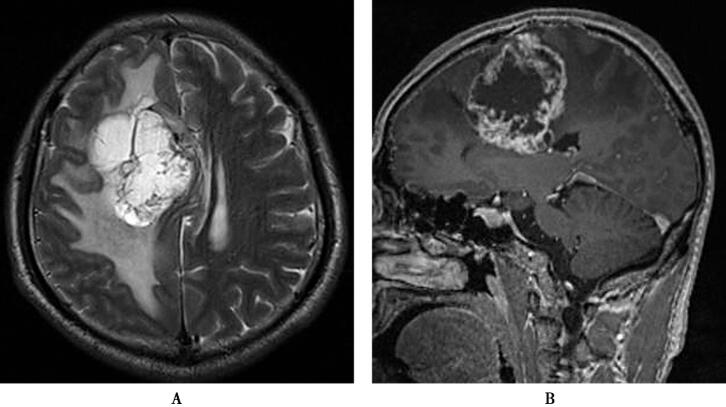

图1 大脑浆细胞瘤

右侧额叶形状不规则的异常信号灶,占位效应明显,周围脑组织广泛水肿,增强后病灶呈“花环样”不均匀强化,周围水肿区域无明显强化